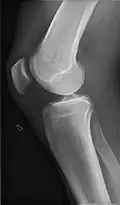

- Knee - AP and Lateral. Intra Condular projections on request

-

Right knee, anteroposterior -

Right knee, lateral -

Patella, (slightly skew) skyline